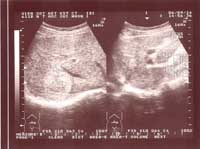

Một số hình ảnh siêu âm tổn thương gan do sán lá gan lớn:

Hình ảnh 1: Khối tổn thương gan do SLGL điển hình, Khối lớn với micro ap xe bên trong | Hình ảnh 2: Khối tổn thương gan do SLG điển hình: Khối lớn và có nhiều micro áp - xe bên trong |